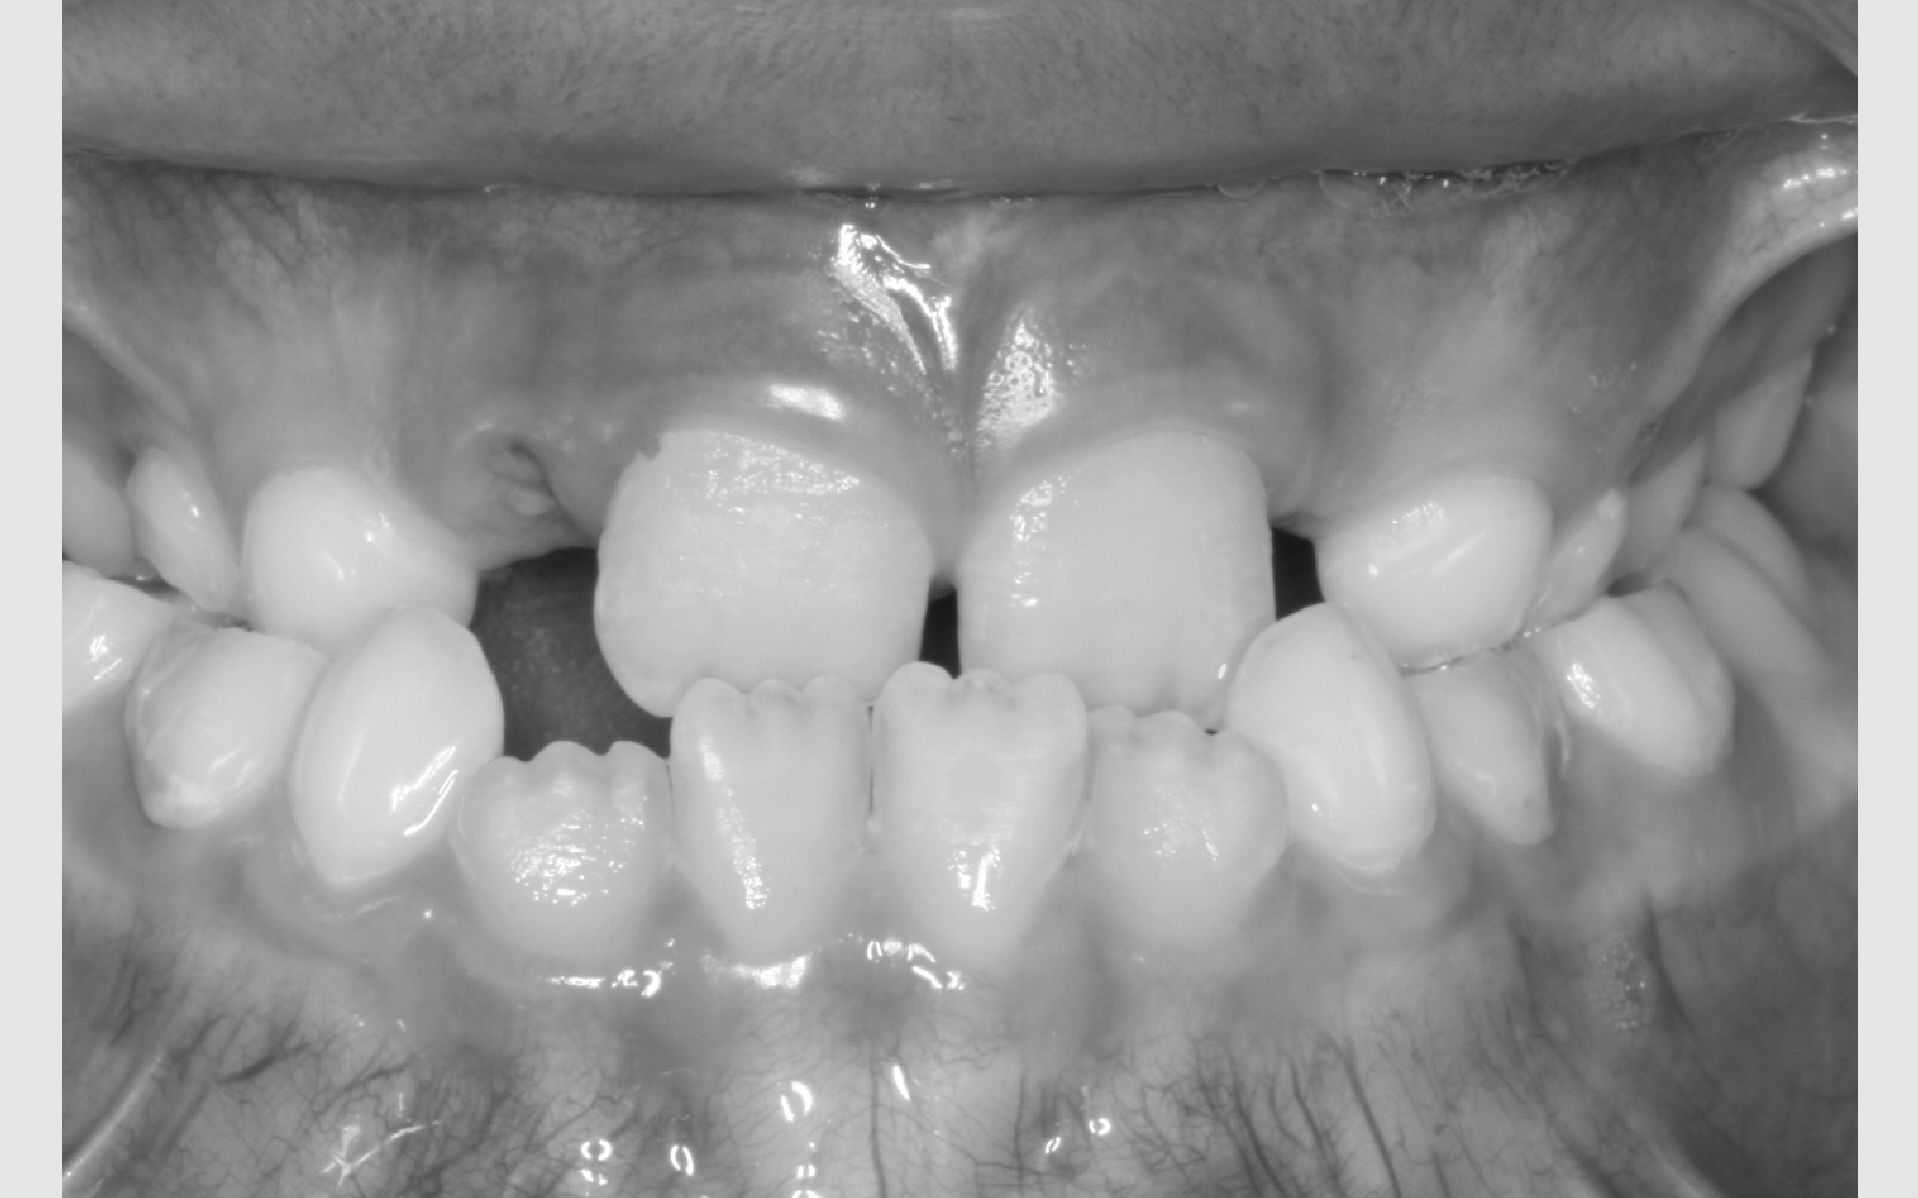

Studiemateriale, består af modeller, fotos og røntgenbilleder af tænder og ansigt. Der bliver også udleveret et helbredsskema, som skal udfyldes på stedet. Det er vigtigt at vide, om jeres barn er sundt og raskt, eller om der er særlige hensyn, vi skal tage - eksempelvis til medicin med videre.

Der bliver taget billeder "udenpå og indeni" samt røntgenbilleder.

Dit barn skal selv holde sine læber til side med en læbeholder, mens tænderne bliver fotograferet. Billederne har følgende formål: